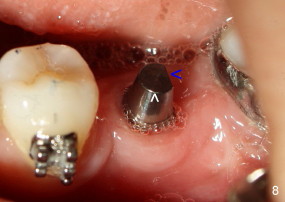

The tooth #19 has been lost for 8 years with tilting of #18 (black line in Fig.1). A 6x8 mm Bicon implant (3 mm post) was placed as distal as possible (I in Fig.2). Three months later, the implant was uncovered with evidence of osteointegration (arrowheads in Fig.3). A 4x6.5 mm 0 degree non-shouldered abutment with 3 mm post (A) was inserted into the implant well. The flat surface of the abutment needed to face distal in order to seat the abutment without interference. The implant/abutment complex was used as an anchorage to upright #18. The tooth #17 was extracted prior to orthodontic treatment (compare Fig.5,6 vs. 1-3). A bracket was bonded to Jet temporary crown of #19 and open coil spring was placed between #18 and 19. In the first two months, distalization of #18 is limited (between black and white lines in Fig.4), partially due to the fact that the bracket of #19 was debonded quite easily. A premolar band (B in Fig.5) was cemented to the temporary crown of #19. In another two months, the tooth #18 was pushed to desired position (arrowhead) under the tension of open coil spring (*). The mesial crest height of #18 was increased during uprighting (arrow, as compared to Fig.1-3). A new temporary crown was fabricated to fit the enlarged space of #19 with cementation of a molar band. The next problem is that the new molar temporary crown was easily dislodged from the 4x6.5 mm abutment even with a permanent cement. A larger abutment (5x6.5 mm) was used (Fig.6), with relining the temporary crown. The upper end of the larger abutment has sharp edge (Fig.8: white arrowhead, as compared to rounded edge of the smaller abutment (Fig.7). This may also contribute to better retention. In another 3 months, the temporary crown was dislodged again. An even larger abutment (6.5x6.5 mm with two flat surfaces (blue arrowheads in Fig.9) was adopted.